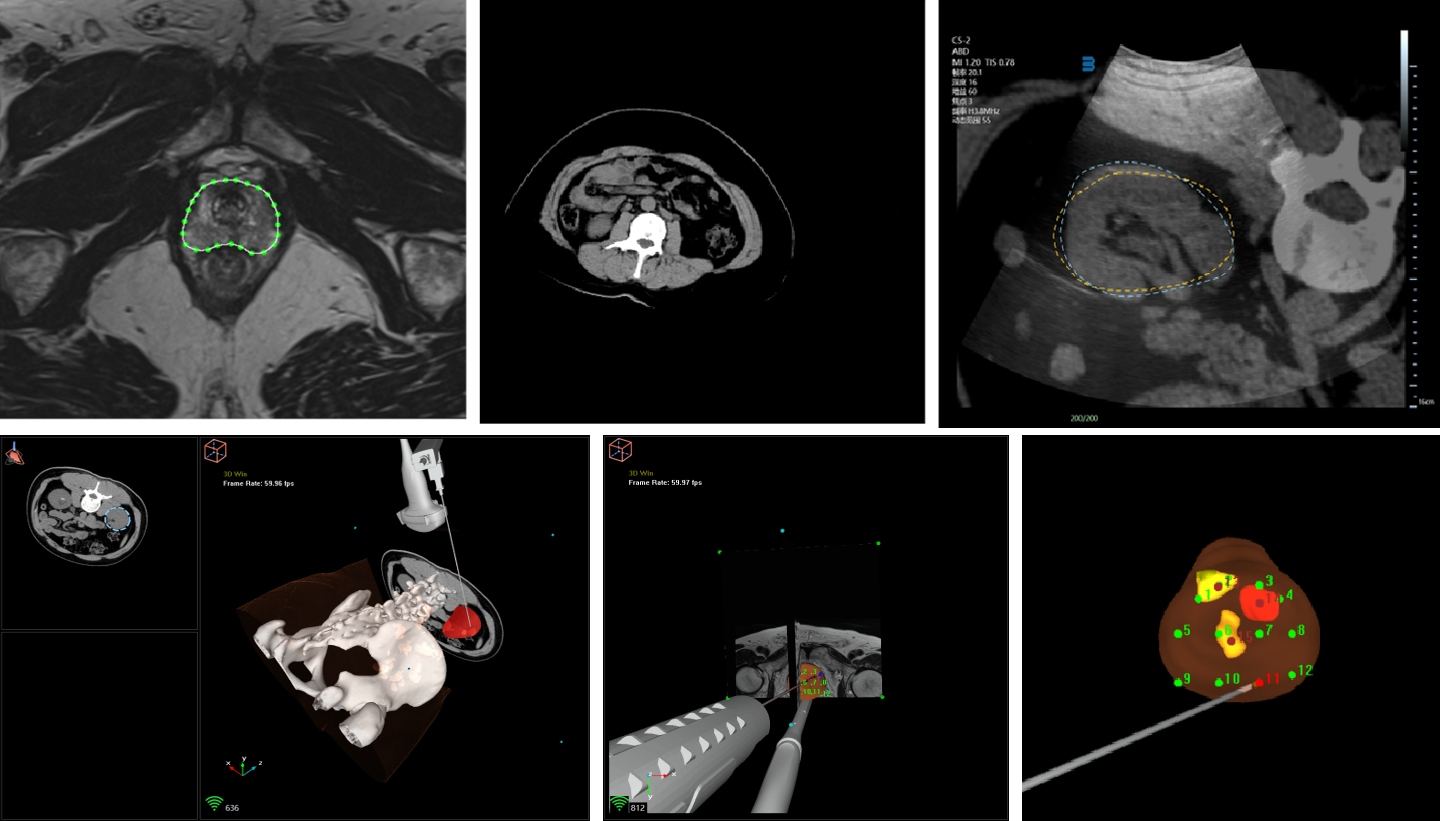

VENUS影像融合功能能将静态 CT/MR 序列与动态超声实时融合,直观呈现 3D、2D 器官解剖结构,高效便捷的辅助医生定位病灶、规划穿刺路径,快速引导建立精准介入通道。卡本VENUS证书获批,意味着国产医疗影像融合器械空白被正式弥补。

医疗设备的创新发展,临床需求是基石。卡本VENUS从临床以及患者的需求出发,一举解决了非血管介入领域的三大难题——快速定位病灶、精准规划手术路径,以及快速引导建立精准介入通道,为患者提供更为精准的治疗方案。凭借重叠式精准融合、器官分割、针尖动态识别、病灶追踪勾勒、靶向穿刺引导等技术,卡本VENUS能将非血管介入手术可视化、术式简单化,提高手术安全性和效率的同时,也满足了患者精准化治疗的要求。